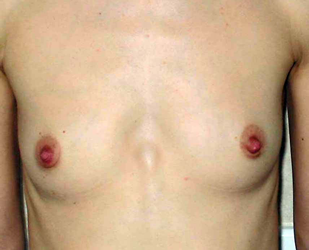

L’augmentation mammaire par pose d’implants est la seule alternative pour augmenter significativement et harmonieusement la taille des seins.

Les patientes de cet album ont des voies d’abord différentes, comme des tailles de prothèses ou de positionnement par rapport au muscle pectoral.